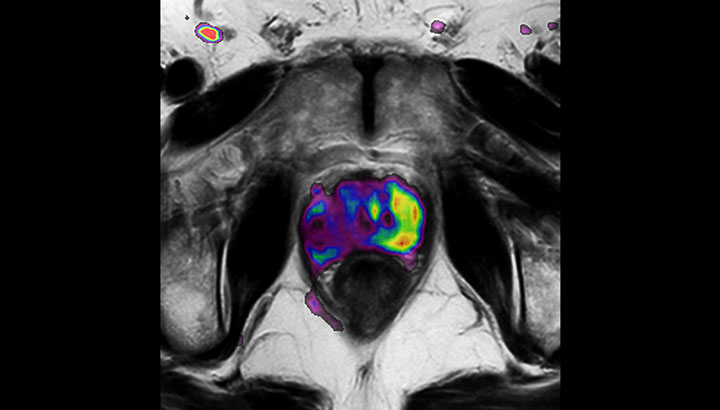

In addition to anatomical imaging, MRI offers the ability to obtain functional information that is beneficial for tumor detection and delineation, and for response monitoring.

Diffusion-weighted imaging (DWI) for example depicts areas of high signal intensity in soft tissues that are indicative of the restricted water mobility (i.e., diffusion) of a tumor and can also be used to identify lymph nodes. Changes in the tissue’s or lesion’s apparent diffusion coefficient (ADC) can provide insights that help predict the tumor’s response to radiotherapy.